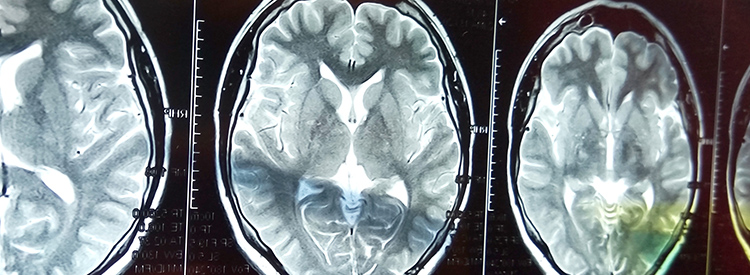

中風(fēng)治療進(jìn)展緩慢。如果在最初幾分鐘內進(jìn)行治療,可以在急診室或醫院使用特殊藥物(阿替普酶或組織纖溶酶原激活劑)來(lái)逆轉或限制缺血性中風(fēng)造成的損害。這種藥物可以分解阻塞血管的凝塊。如果在最初的幾分鐘到幾小時(shí)內使用,可以避免或限制對大腦的任何損害。在使用阿替普酶之前,必須進(jìn)行 CT 成像來(lái)確定中風(fēng)類(lèi)型,以確認中風(fēng)不是出血性的。由于阿替普酶會(huì )分解血栓,因此如果用于出血性中風(fēng),可能會(huì )導致嚴重惡化或死亡。有時(shí)會(huì )治療出血性中風(fēng)以避免進(jìn)一步出血。